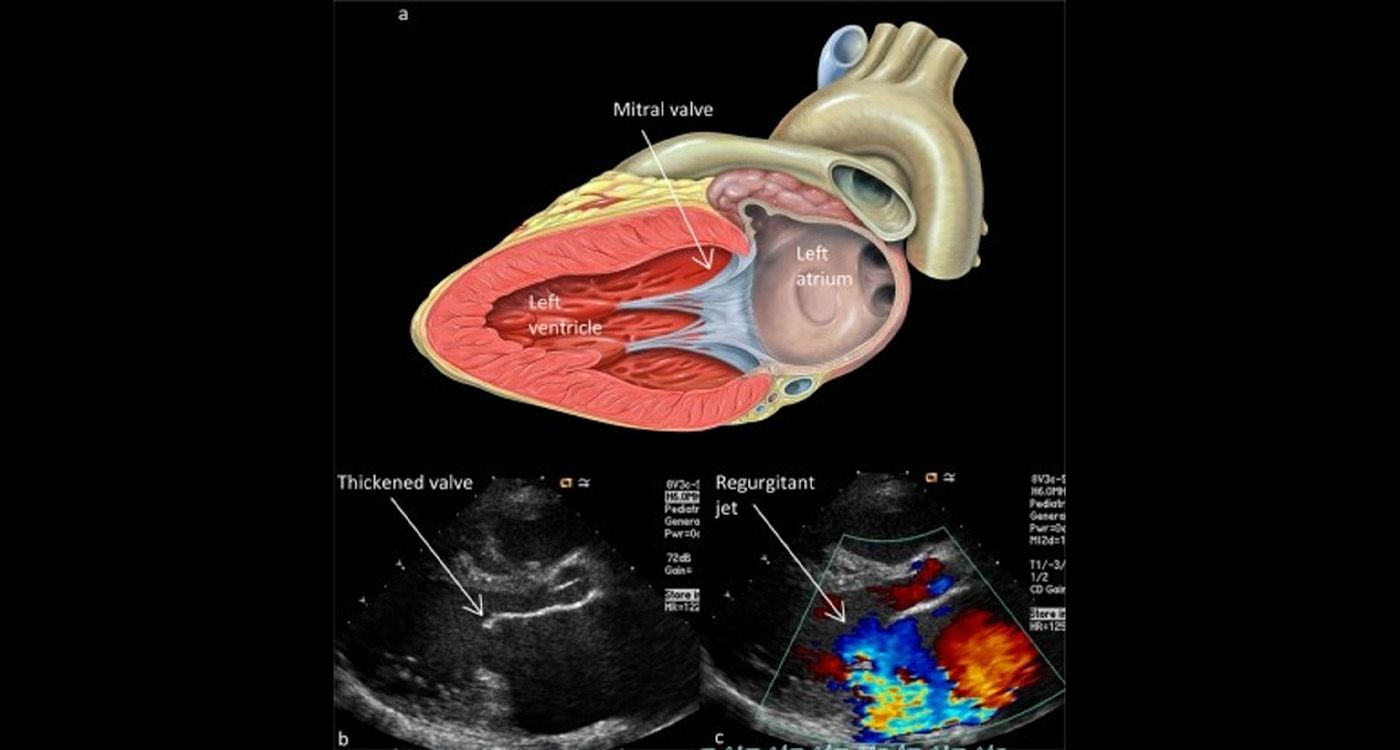

Préserver la valve, réparer l’aorte

Le 25 septembre 2024, l’Hôtel-Dieu de France a réalisé une procédure de type David (équipe dirigée par Ziad Khabbaz): on remplace l’aorte ascendante tout en gardant la valve aortique. Intérêt concret: éviter une valve mécanique (anticoagulation à vie) ou une bioprothèse moins durable. C’est la tendance actuelle: préserver quand c’est possible.